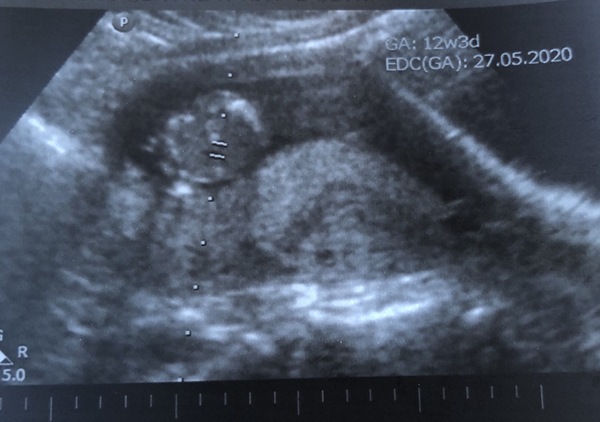

RacBell · 18/11/2019 14:01

Hi all, just had my 12 week scan. Baby wasn’t behaving today and wouldn’t budge from curled up position and doing a head stand but otherwise all looks perfect. Given due date 29/5. Has anyone else been given this date? I’ve got a sneaky feelings it’s a girl but don’t want to convince myself too much 😩 I already have 2 boys ☺️